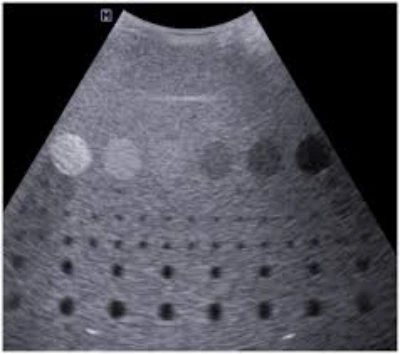

Entenda a importância da calibração de ultrassom para a precisão dos exames clínicos

A calibração de ultrassom envolve ajustes técnicos e inspeções periódicas que asseguram a precisão das imagens obtidas nos exames clínicos .

Técnicos especializados realizam intervenções preventivas, corrigindo variações e mantendo o desempenho ideal dos aparelhos.

Esse serviço reduz falhas, prolonga a vida útil do equipamento e permite que hospitais e clínicas realizem diagnósticos confiáveis.

Com calibração adequada, os procedimentos médicos ocorrem com segurança e eficiência, fortalecendo a confiança de profissionais e pacientes.